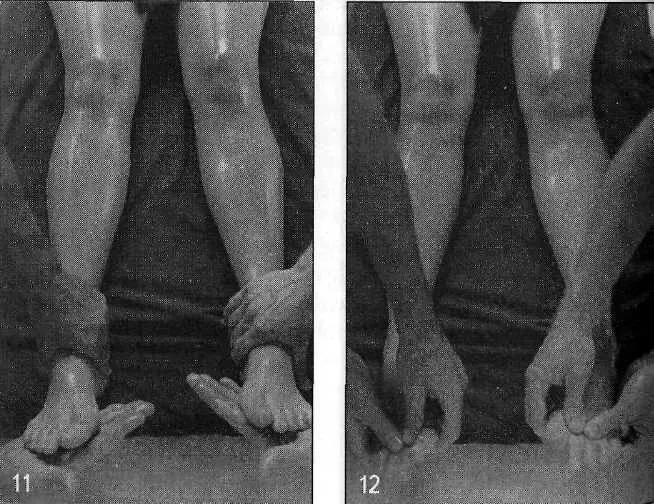

Бахья снехана представляет собой последовательность массажных движений, выполняемых в следующих направлениях: от пупка к голове, от головы к пупку, от пупка к ногам и от ног к пупку — на передней и задней поверхностях тела. Давление, прилагаемое массажистом, различается в зависимости от массируемой области (присутствия точек мармы). Согласно аюрведе, в точках мармы происходит соединение между физической материей тела и его внутренней мудростью. Стимуляция мармы оживляет и координирует взаимодействие субдош ваты, а следовательно, гармонизирует все нейрофизиологические процессы в организме.

По сравнению с башпа, нади представляет собой более проникающую разновидность воздействия, так как пар загоняет тепло и масло от бахья снеханы глубоко в ткани через поры кожи. Хотя применять нади сведану можно на всей поверхности тела, особое внимание уделяется крупным и сложным суставам для улучшения их подвижности. Обычная продолжительность процедуры составляет 5–7 минут. Безотносительно панчакармы, ее можно использовать в сочетании со снеханой для избавления от боли, мышечных спазмов и ригидности в конкретных областях тела, особенно — конечностей. Такое лечение хорошо успокаивает боли в спине при миозите и радикулите, в тазобедренных и коленных суставах.